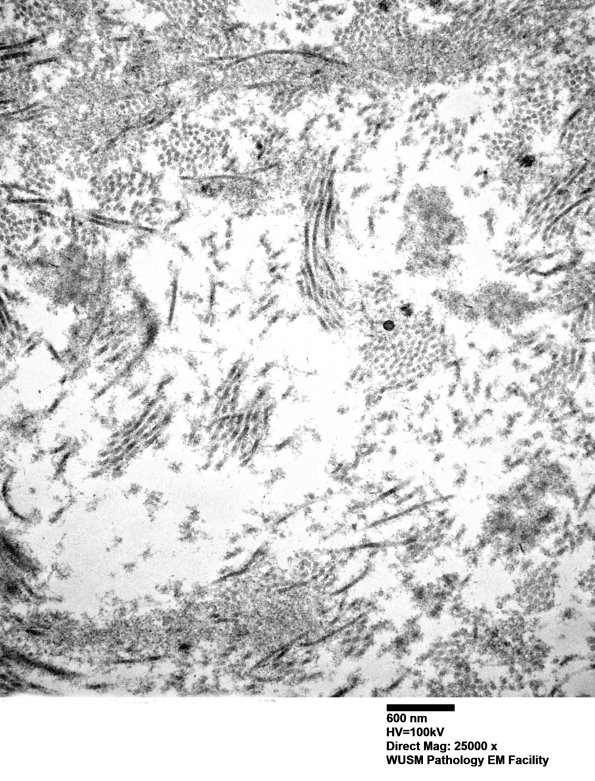

Higher magnification of elements of the RB shown in image #2H1 demonstrating the admixture of collagen and oxytalan. (electron micrographs)